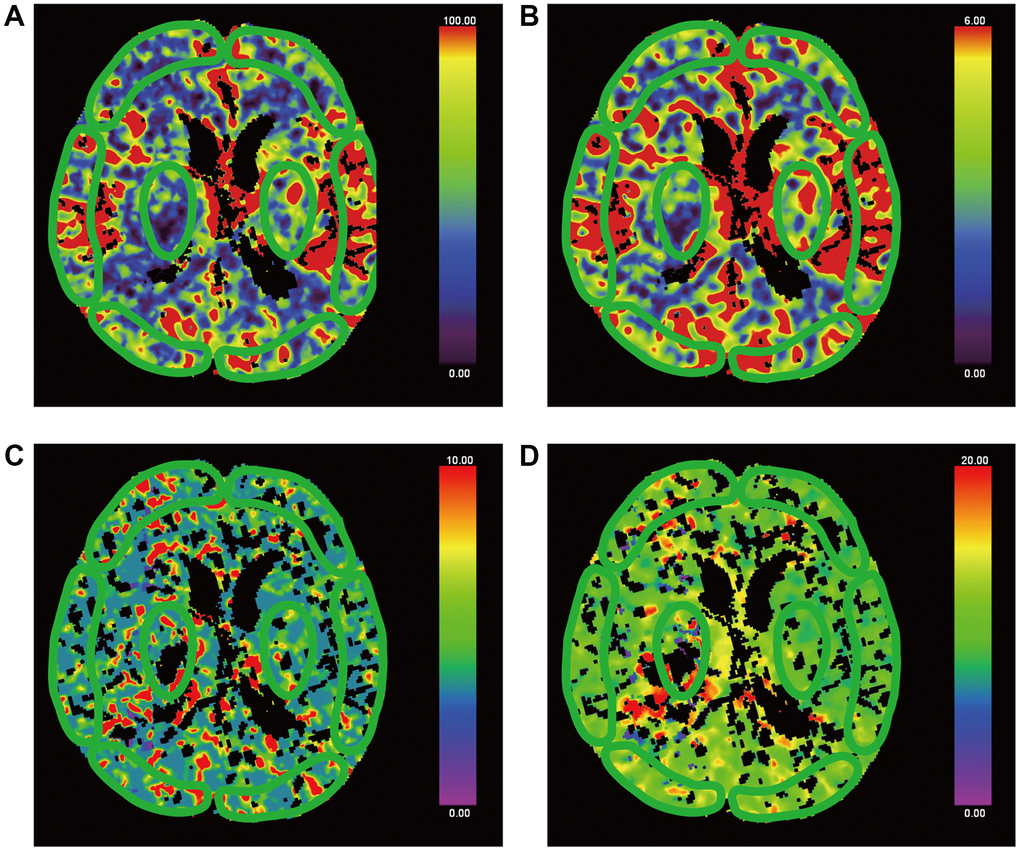

Brain pCT was measured by two clinicians experienced in the imaging diagnosis of neurological disorders. A workstation (Syngo.via, version VA30A; Siemens Healthineers) was used for post-processing. The internal carotid artery was chosen for the inflow artery, and the superior sagittal sinus was used as the outflow vein to generate a time radiodensity curve of the blood. Then, CBF, CBV, MTT and TTP perfusion maps were automatically created. Avoiding the great vessels, the same clinicians were responsible for the selection of regions of interests (Figures 3 and 4) in bilateral gray and white matter in the frontal, occipital, and temporal lobes, as well as in the thalamus, brainstem, the damaged part, and contralateral to the damaged part. Meanwhile, the mean CBF, CBV, TTP and MTT in each ROI were calculated. Absolute values are shown in colour maps (CBF is reported in mL/min/100 g of brain tissue, CBV is reported in mL/100 g of brain tissue, and MTT and TTP are reported in seconds).

Figure 3. False-colour pictures of a 76-year-old MCS− man after right thalamus hemorrhage at the basal ganglia level. The affected side is right. The damaged part is right thalamus. (A) The CBF map of the bilateral frontal cortex, temporal cortex, occipital cortex and thalamus, (B) the CBV map, (C) the TTP map and (D) the MTT map.

Figure 4. False-colour pictures of a 76-year-old MCS− man after right thalamus hemorrhage at the pontine level. The affected side is right. (A) The CBF map of the brainstem, (B) the CBV map, (C) the TTP map and (D) the MTT map.